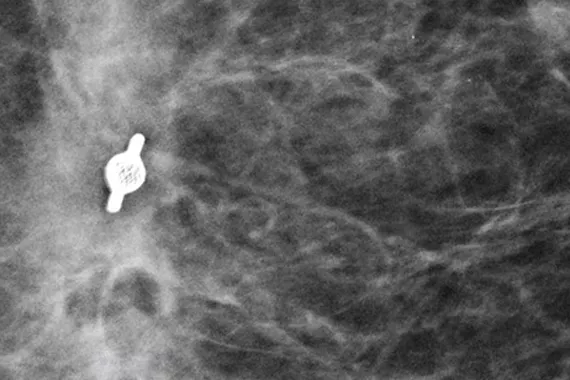

The Hologic range of biopsy site markers come in multiple shapes, gauges and lengths. The markers are compatible for use with x-ray, ultrasound and MRI guided biopsies.  All markers come with an ergonomic and easy to use deployment device included.

Intelligently designed to provide long-term visibility. All Tumark Markers are non-bioabsorbable, biocompatible permanent markers offering excellent visibility and are designed to minimise movement.1

Research shows that the Tumark Professional X, Q and Vision biopsy site markers are accurate and easy to use.1

of markers deployed accurately to the intended area1